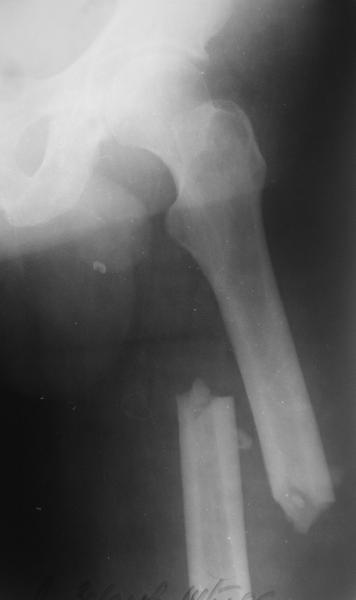

Изначально у оперируещего хирурга были только теоретичесике представления о ЗИМО с блокированием, планировался компрессионно-динамический остеосинтез стержнем S2 (Stryker).

Во время операции ни стол ортопедический,ни ДРУ не применялось (думалось, что сделают все на руках!)

Изначально была выбрана не правильная точка введения стержня, в связи с чем в конце, я подчеркну, в конце операции произошло из-за напряжения между прокимальным концом канала бедра и стержнем разрушение в/3 бедра.

Проволока наложена потому, что при введении штифта не прошли эту зону римером и произошли сколы на концах отломков.

Под ЭОП во время операции такого смещения не было. Мы бы конечно не отпустили этого больного с такой картиной (сами бы что-то сделали или к вам отпр).

Почему не сделали R-gr? Все банально для таких больниц как наша - не работал R-аппарат в течении 3х недель.(я сам увидел эти снимки у вас)